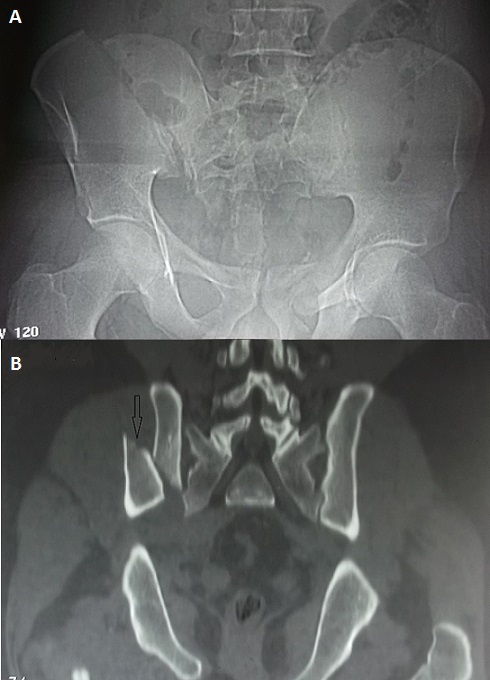

A historic “open book fracture”

"Open book fracture" is rare. It is one of the most dangerous pelvic fractures. It is usually associated with abdominal, vascular and nervous injuries requiring a multidisciplinary team for its management. Its treatment is mainly surgical. Only some cases are published in recent literature. The mechanism is usually complex and the consequences usually dramatic. We report in this case a very rare image of an open book fracture which occurred in a young thirty old man. He was admitted to the emergency department of our hospital after a work accident. He was hit by a heavy (500 kg) charge in his back with impact to the groin in the manufactory where he works. He was transferred by a non-medical transfer to our emergency department. At initial examination, he had a deformed pelvis with moderate bleeding. We observed a large hematoma in his back. The standard pelvis radio X ray (A) revealed a disruption of the pelvic ring with a "third fragment". Pelvic CT scan showed this third fragment (B). There was a complete fracture of the right iliac wing with a sacroiliac joint disruption. The right and the left halves of the pelvis are separated at front and rear. The front was opening more than the rear. It seemed like an open book and it is called "open book" pelvic fracture. The patient was managed initially in the emergency room with fluid challenge and analgesia. He had then urgent multidisciplinary surgery with external fixation with a good outcome.